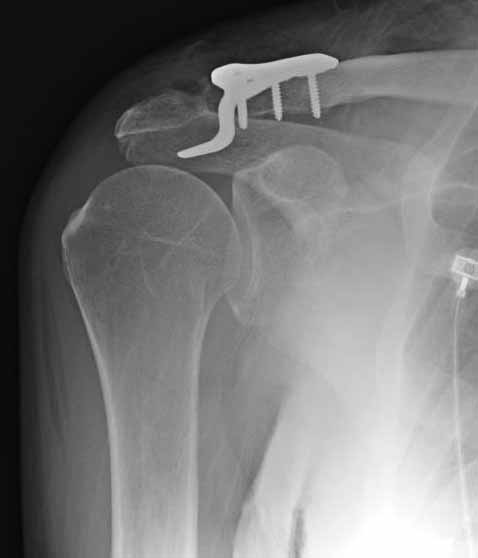

Но это не помешало успешно пациента прооперировать.

1.JPG

foto

2.JPG

foto 3

3.JPG

foto 4

4.JPG

foto 5

коллаж у меня не получился, пришлось отдельно рентгенограммы присоединить :-))

5.JPG

Замечание понял, спасибо и нормальные рентгенограммы, молодец!

Во вторых, это хорошо что нашли длинную пластину, я об этом писал "пластина короткая, не покрывает медиальный диафизарный фрагмент ключицы", и у нас не получилось, пластина не выдержала...

На конференции EFORT в Копенгагене поднимался вопрос о пластинах для остеосинтеза ключицы с крючком. Не имею возможность осветить все что там услышал. Но у меня появилось понимание о импиджмент синдроме, о необходимой длине крючка, о правильном позиционировании пластины, о лизисе акромиона и т.д.

Мне кажется что если понять принципы, то можно использовать и короткую пластину. Что мы с успехом применяли раньше и применяем сейчас, но уже более осознанно. В вашем случае Серж, у меня стойкое ощущение, что необходима дополнительная иммобилизация, так как неправильно выбрано место введения крючка и при ранней нагрузке пластину просто вырвет. Если вам несложно не могли бы вы продемонстрировать прямую и боковую проекцию и в более хорошем качестве. ИМХО

На чем у Вас обосновано" стойкое ощущение, что необходима дополнительная иммобилизация, так как неправильно выбрано место введения крючка"?

Теоретически можно использовать и короткую пластину. Но на операции дистальный отломок( акромиальный конец ключицы ) был коротким и оскольчатым, поэтому крючок и использование там блокированных винтов в пластине было очень уместно. Доступ - "сабельный удар". Точка введения крючка - сразу сзади от ключично-акромиального сустава. Если честно - больше внимания уделяли репозиции отломков и адекватному расположению пластины на ключице :-) крючок проверяли на прочность фиксации за акромион и полный объем движений в плечевом суставе. После операции рука на косынке, нагрузку ограничили. Снимки есть в нормальном разрешении, но здесь "размер файла не превышал 75 кб." Если есть необходимость залью в пикассу...